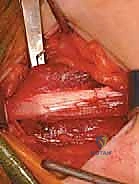

الإجراء الجراحي التفصيلي: إطالة العضلة الحرقفية القطنية والعضلات المقربة

عندما يصبح التدخل الجراحي ضرورة، يقوم الأستاذ الدكتور محمد هطيف بإجراء العملية بأعلى معايير الدقة الجراحية. تُعرف هذه الجراحة بـ (Soft Tissue Release of the Hip)، وتتمثل أهدافها في استعادة التوازن العضلي وتوسيع نطاق الحركة.

1. إطالة العضلات المقربة (Adductor Tenotomy / Release)

يتم إجراء شق جراحي صغير جدًا (غالبًا باستخدام تقنيات الجراحة طفيفة التوغل) في منطقة الفخذ الداخلية. يقوم الدكتور هطيف بتحديد وتر العضلة المقربة الطويلة (Adductor Longus) بدقة، ويتم قطعه أو إطالته. في بعض الحالات الشديدة، قد يتم تحرير جزء من العضلة المقربة القصيرة (Adductor Brevis) والعضلة الناحلة (Gracilis).

النتيجة الفورية: بمجرد تحرير الوتر، تزداد زاوية فتح الساقين (Abduction) بشكل ملحوظ على طاولة العمليات.

2. إطالة العضلة الحرقفية القطنية (Iliopsoas Lengthening)

يتم الوصول إلى وتر العضلة الحرقفية القطنية إما من خلال نفس الشق المستخدم للعضلات المقربة، أو عبر شق صغير منفصل في الجزء الأمامي من الورك. يقوم الجراح بقطع الجزء الوتري من العضلة (Tenotomy) مع ترك الألياف العضلية سليمة. هذا يسمح للعضلة بالتمدد دون أن تفقد وظيفتها الأساسية تمامًا.

النتيجة الفورية: يتمكن الطفل من فرد فخذه بالكامل، مما يصحح وضعية الانحناء للأمام.

تقنيات متقدمة لضمان الأمان

يستخدم الأستاذ الدكتور محمد هطيف تقنيات ميكروسكوبية وأدوات دقيقة لضمان عدم المساس بالأعصاب والأوعية الدموية الهامة المجاورة (مثل العصب السدادي - Obturator Nerve). هذا المستوى من الدقة هو ما يميز الجراح الخبير ويضمن تعافيًا أسرع وأكثر أمانًا للطفل.